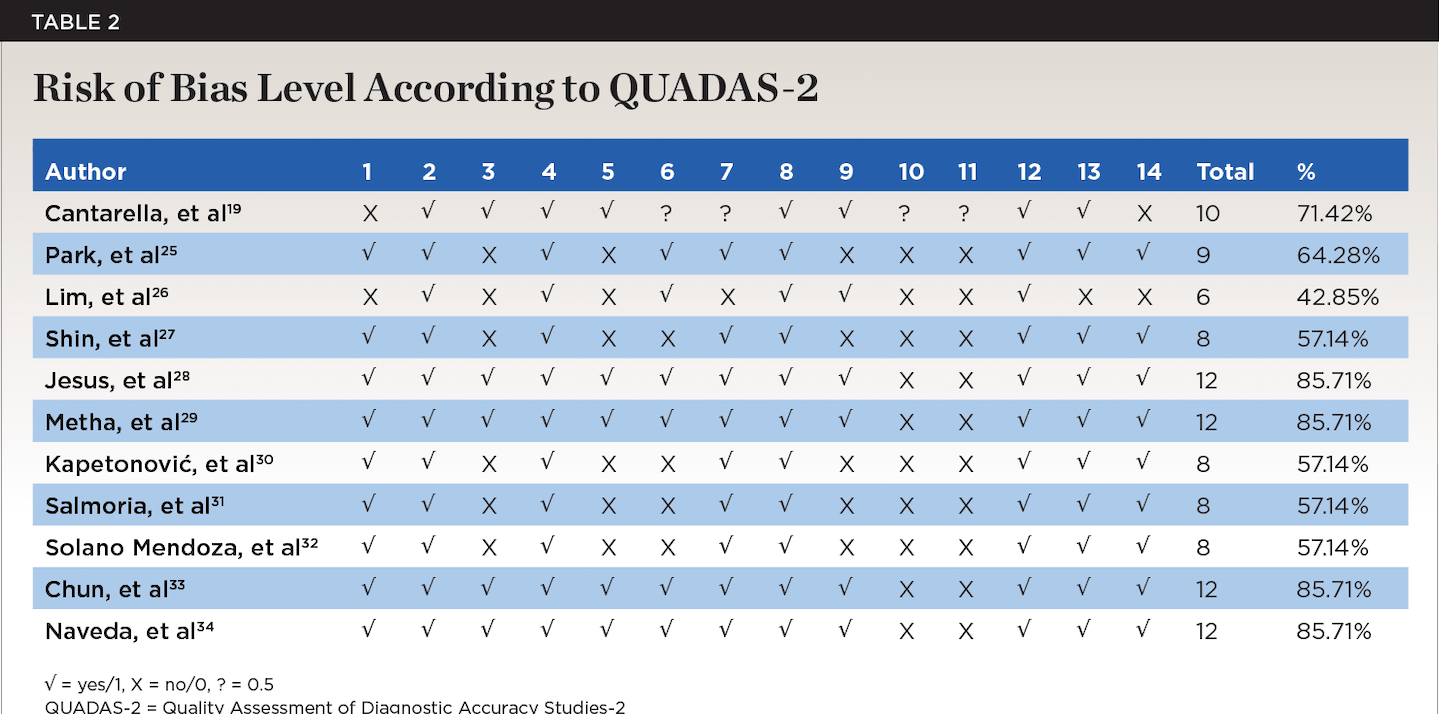

For the assessment of the quality of the articles, the present authors used the Quality Assessment of Diagnostic Accuracy Studies-2 (QUADAS-2) scale,35 with a moderate-to-low risk of bias (Table 2).

Upon reviewing the remaining 52 articles, 41 were excluded due to lack of scientific evidence, as they either were case reports or lacked conclusive findings. Therefore, the articles included in the present review amounted to 11 total, with a moderate-to-high level of evidence and a moderate-to-low risk of bias, as reflected in Table 1 and Table 2, respectively.

Risk of Bias in the Articles

The various domains for assessing the risk of bias in each study are presented in Table 2. The QUADAS-2 scale was used. The studies were heterogeneous, with moderate-to-high methodological quality, and all were considered to have a moderate-to-low risk of bias. Four studies were of high quality. Six studies were of moderate quality, meeting 50% to 64% of the QUADAS-2 criteria, and one study was of low quality. The weaknesses were reflected in the lack of comparison with the gold standard and the absence of blinding.